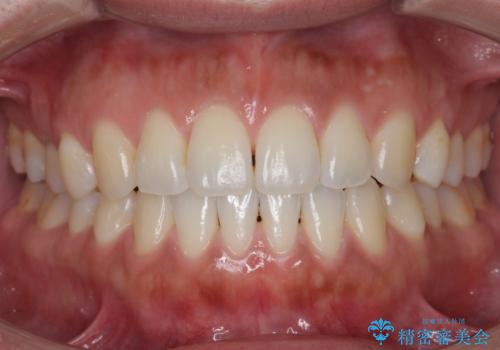

受け口、すきっ歯を インビザラインで モニター治療

- 前歯のすき間と受け口を気にして来院。

マウスピースでしっかり閉じています。

下の前歯を後方に移動するため、ゴムを上下のマウスピースにかけてもらいました。